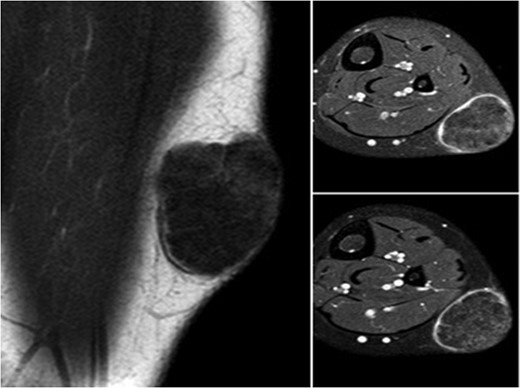

A 10-year-old boy presented with a 3-month history of pain and swelling in the left leg. Physical examination showed a 3 × 4 cm2 solid and mobile mass along the posterior aspect of the left leg. There were no history of trauma, weight loss or previous inflammatory disease. Radiographs showed calcification on the posterolateral side of the left cruris (Fig. 1). MRI indicated a solid soft tissue mass in the posterolateral side of the left cruris, which was observed to be hypointense in the T1A series, and hyperintense in the T2A series. The mass had regular margins, and exhibited peripheral contrast enhancement with a 41 × 30 × 27 mm3 size (Fig. 2). Lipoma, epidermoid cyst, sebaceous cyst, calcified hematoma and giant-cell tumor were considered in differential diagnosis. Incisional biopsy was performed. Histopathological examination confirmed as pilomatrixoma (Fig. 3). Thus, a complete resection of the mass was performed. There has been no recurrence, either clinically or radiologically, in subsequent 1-year period.

Lesion showing development in the form of irregular islands made up of a nucleate eosinophilic shadow cells, with the spindle-like fibroblastic cells between them.